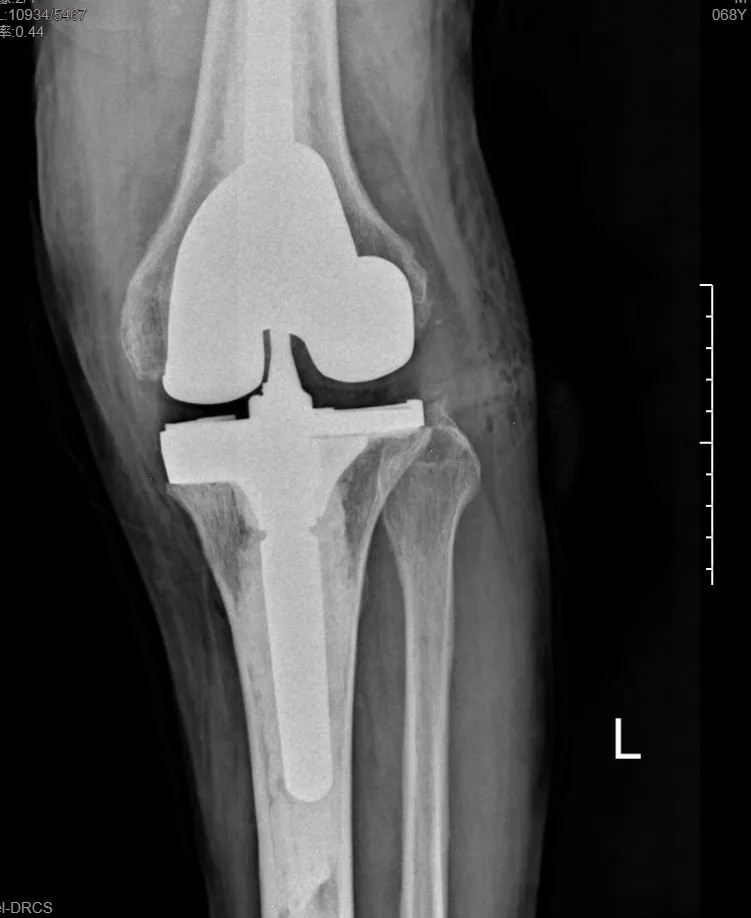

本次手術(shù)的核心,是采用了Evolution® ECCK膝關(guān)節(jié)翻修系統(tǒng)。該系統(tǒng)專為應(yīng)對翻修手術(shù)中常見的嚴重骨缺損、韌帶功能不全等極端復(fù)雜情況而設(shè)計。

其模塊化的組件提供了前所未有的靈活性,就像一套高精度的“工程套件”,允許醫(yī)生在術(shù)中根據(jù)實際骨缺損情況,自由組合不同尺寸的墊塊、延長桿等部件,實現(xiàn)關(guān)節(jié)線和力學穩(wěn)定性的個體化重建。

尤為重要的是,該系統(tǒng)保留了內(nèi)軸型假體的設(shè)計哲學,在重建關(guān)節(jié)穩(wěn)定性的同時,努力模仿了人體膝關(guān)節(jié)自然的運動方式(內(nèi)軸穩(wěn)定性、外側(cè)活動性),旨在讓患者術(shù)后不僅能走,還能走得更舒適、更自然。

集多項前沿科技于一體的精準手術(shù),帶來了令人欣喜的結(jié)果。術(shù)后第一天,在醫(yī)生指導(dǎo)下,張先生便能夠借助助行器下地站立、邁步行走。

“感覺非常好!膝蓋那里終于不痛了,而且自己能控制它了。”張先生的喜悅之情溢于言表??焖俚墓δ芑謴?fù),極大地增強了他的康復(fù)信心。